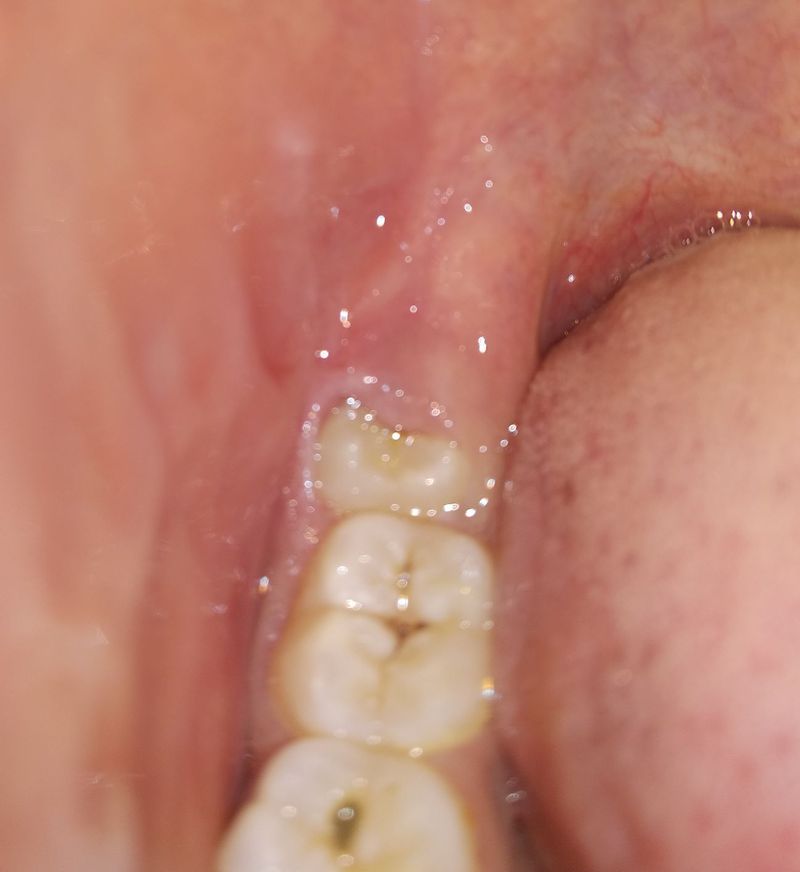

I have an problem with my wisdom teeth , on my right down side of the mouth the wisdom teeth comes up and it is half embedded in the jaws and Half part is only visible When I took the X-ray of it it shows that it's completely mature and this will be it's final state but due to this imperfection it's creating problems such as swelling , huge pain , I'm not able to eat and a little pain in head . Please give me some solution , how I can get rid of it . I consulted to an nearby doctor and he told me to remove the wisdom teeth , is it correct or is there any other solution ?

I work for a dental office and it must be removed... It is very common... We do a lot of these surgeries